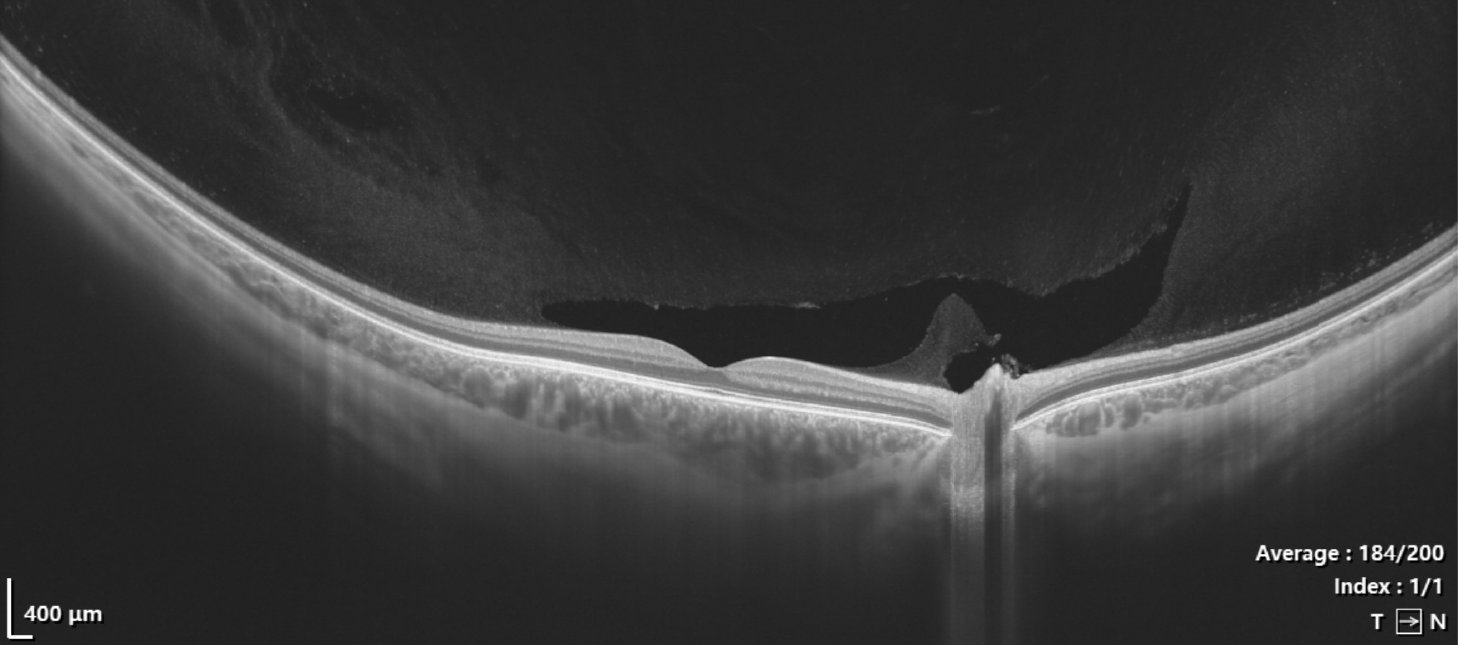

…welche zur Diagnose und Überwachung verschiedener Augenerkrankungen eingesetzt wird. Diese nicht-invasive Methode ermöglicht eine detaillierte Darstellung der Gewebestrukturen im Auge, insbesondere der Netzhautschichten.

Bei einer OCT wird ein spezieller Scanner verwendet, der mithilfe von Lichtwellen die Netzhaut und andere Augenstrukturen in hoher Auflösung abbilden kann. Das Licht wird in das Auge gesendet, wo es von den verschiedenen Gewebeschichten reflektiert wird. Die reflektierten Lichtwellen werden dann vom Scanner erfasst und in ein digitales 3D-Bild (Tomografie) umgewandelt. Das akustische Pendant dazu ist die Sonographie.

- Netzhauterkrankungen: Die OCT kann Veränderungen in den verschiedenen Schichten der Netzhaut identifizieren, was bei der Diagnose von Erkrankungen wie Makuladegeneration und diabetischer Retinopathie hilfreich ist.

- Grüner Star: Durch die Beurteilung des Zustands des Sehnervs und der retinalen Nervenfaserschicht kann die OCT helfen, das Glaukom frühzeitig zu erkennen und den Verlauf der Erkrankung zu überwachen.

- Hohe Auflösung: Die OCT liefert detaillierte Bilder der Augenstrukturen in hoher Auflösung.